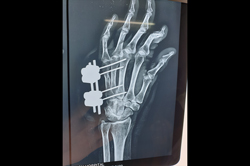

Finger Tip Injury - JESS

Metacarpal Fracture – External Fixator JESS